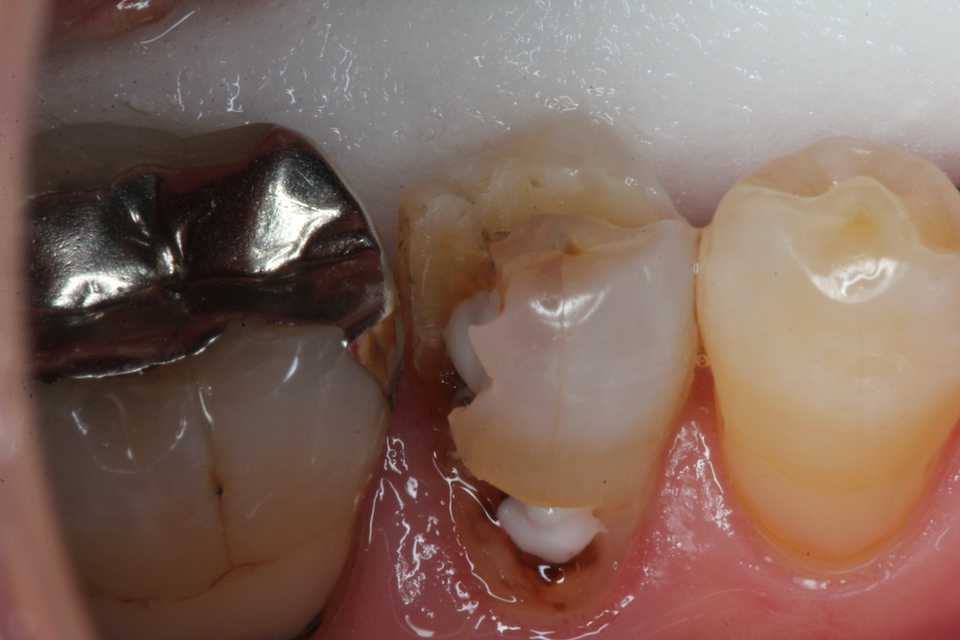

50代女性、右下5、インレー2次カリエス

1mmのマージンより内側は虫歯が残っていても差し支えない。虫歯(軟化象牙質)はα-TCPで再硬化して治るからだ。

ストリップスも使わないでも隣接面窩洞のCR充填は可能だ。

では時系列でどうぞ